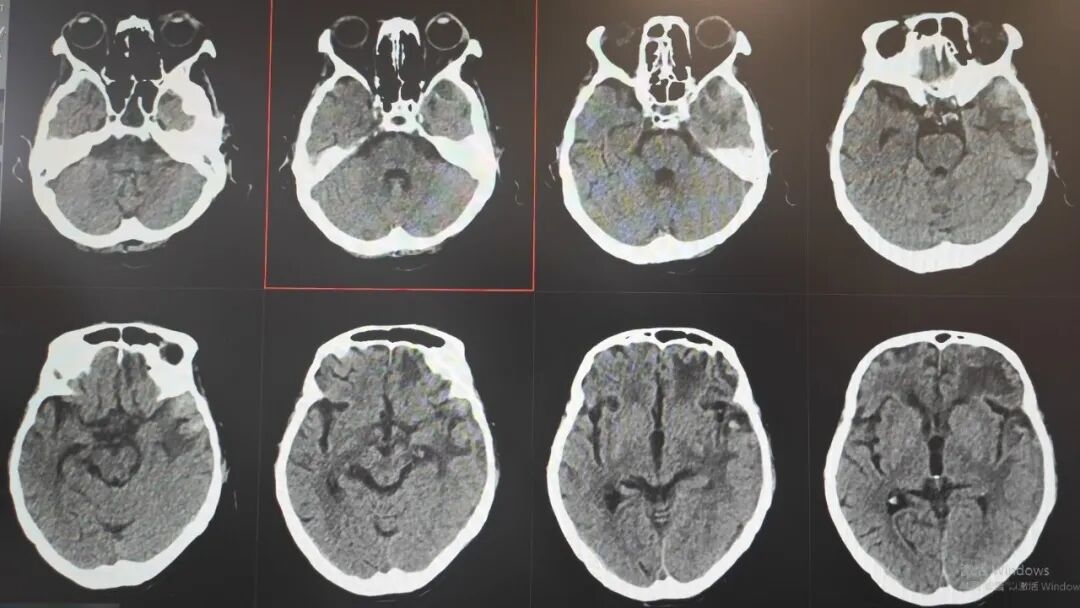

89 岁的吴阿婆(化名)突发意外,被发现时已意识不清、陷入昏迷。家人发现后,紧急将其送往漳州第三医院,检查结果令人揪心:重型颅脑损伤、脑内大面积出血,加之 O 型 Rh(D) 阴性熊猫血、严重贫血······多重致命高危因素叠加,病情十分危重。

如此复杂凶险的状况,在常人看来几乎已是绝境!但漳州第三医院神经外科团队没有放弃,考虑到阿婆身体条件极差、血型特殊、手术风险难以预估,最终摒弃常规开颅方案,为她量身制定了个体化精准保守治疗方案,在绝境中为生命守住一线希望。

那段日子,病情几度反复、险象环生,医护人员寸步不离守在床前,24 小时紧盯生命体征,精细调整每一步治疗方案,昼夜不敢有丝毫松懈。在一次次与死神的拉锯中,他们凭着耐心与坚守,终于等来了转机:阿婆从深度昏迷慢慢睁开双眼,从卧床不起到能在搀扶下缓缓起身,每一个微小的进步,都藏着无数个日夜的坚守与温暖,让绝境之中绽放出生命的微光。